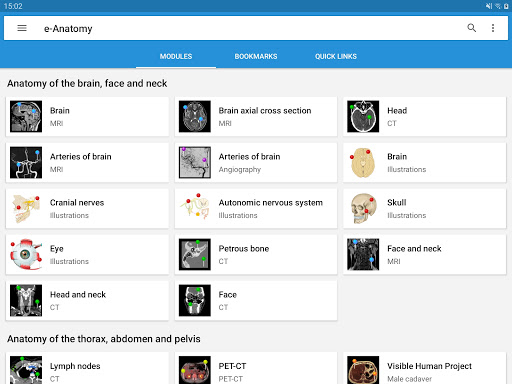

New : You can now filter the modules by region or by content type so you can find the module you are looking for much faster.

-Two new modules : Brain - TOF and Brain Angiography, Atlas of normal neurovascular anatomy of arteries of the brain on a cerebral angiogaphy.-The interface has been reworked.-A new tab named "QuickLinks" is available, dispatching modules in sections of the human body and allowing you to fast travel to the modules you are looking for.-Fixed small bugs.